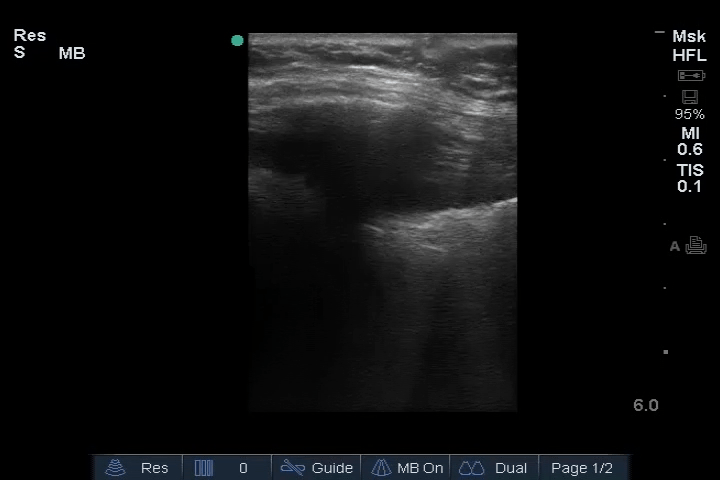

01_Lung_Ant_Right – B-lines